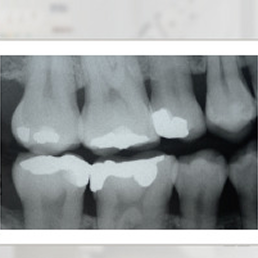

Badanie RTG obrazujące korony zarówno dolnych, jak i górnych zębów w odcinku skrzydłowym pozwala na diagnozowanie próchnicy w tym odcinku oraz ocenić powierzchnie styczne zębów. Stosowane jest w stomatologii zachowawczej oraz protetyce.

- RTG skrzydłowo-zgryzowe – szczególnie przydatne w diagnostyce próchnicy międzyzębowej, powierzchni stycznych oraz ocenie wysokości kości przyzębia. Umożliwia jednoczesne uwidocznienie koron górnych i dolnych zębów trzonowych i przedtrzonowych, dzięki czemu jest często stosowane w stomatologii zachowawczej i protetyce.